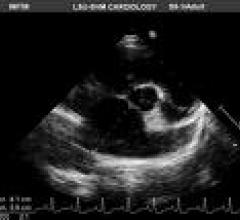

This channel includes news and new technology innovations about cardiovascular ultrasounds. Cardiovascular ultrasounds, or echocardiograms, use ultrasound imaging to provide a picture of the heart.

September 1, 2009 – Echocardiography with Doppler is the method of choice for the noninvasive evaluation of prosthetic ...